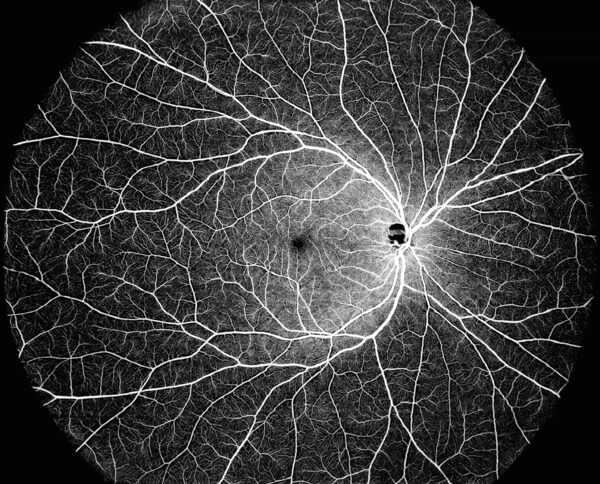

使用DREAM OCT單次拍攝的130度OCTA圖像

DREAM OCT能夠覆蓋超寬視野單次掃描,提供130° OCTA圖像。 DREAM OCT?掃描源12 mm超深度掃描可對(duì)脈絡(luò)膜和視網(wǎng)膜以及大部分玻璃體空間進(jìn)行卓越成像。 超深度前部掃描能力可達(dá)到16.2 mm(空氣中),僅需一次掃描即可完成從角膜到玻璃體前部的整個(gè)前段掃描。 較長(zhǎng)的波長(zhǎng)能夠更好地穿透晶狀體或玻璃體中的混濁區(qū)域。